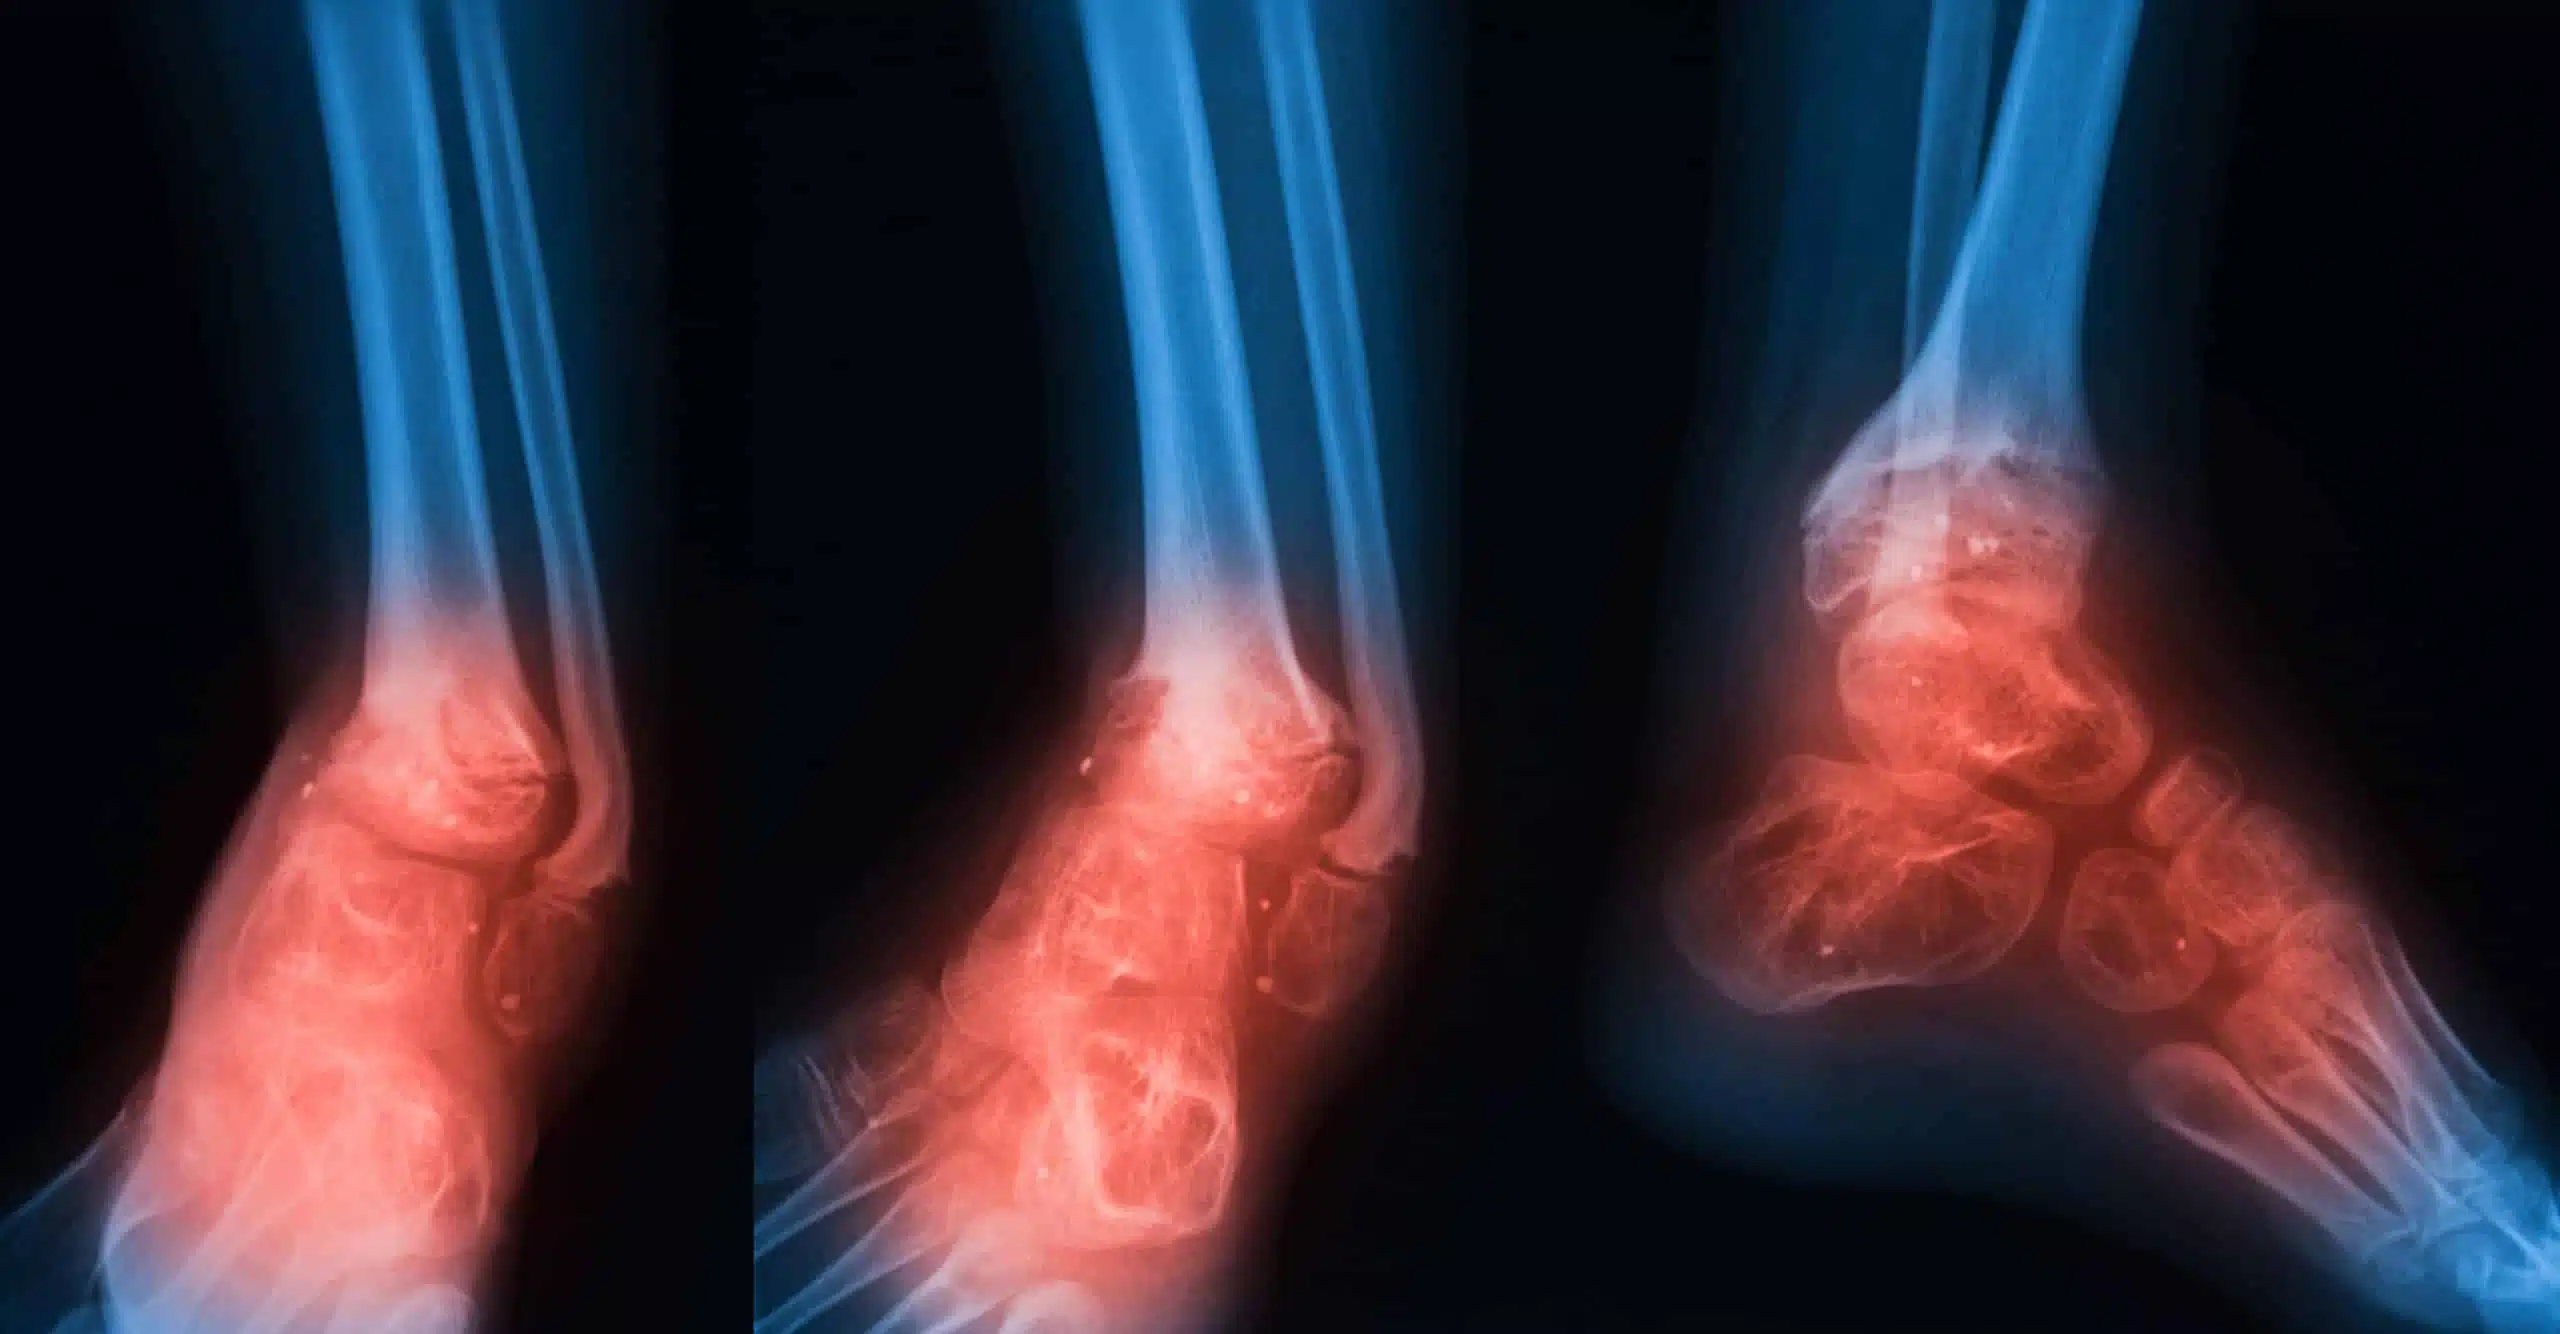

- الفحص بالأشعة: هي مجموعة من الأشعة التي يخضع لها المريض من أجل فحص العظام بشكل مباشر والتأكد من عدم وجو إصابة أو مشكلة مرضية، ومن أهمها الأشعة السينية التي تكشف عن شكل العظام من الداخل، والأشعة التصوير بالرنين المغناطيسي الذي يساعد على فحص الأوتار والأربطة والمفاصل بشكل واضح من جميع الاتجاهات.